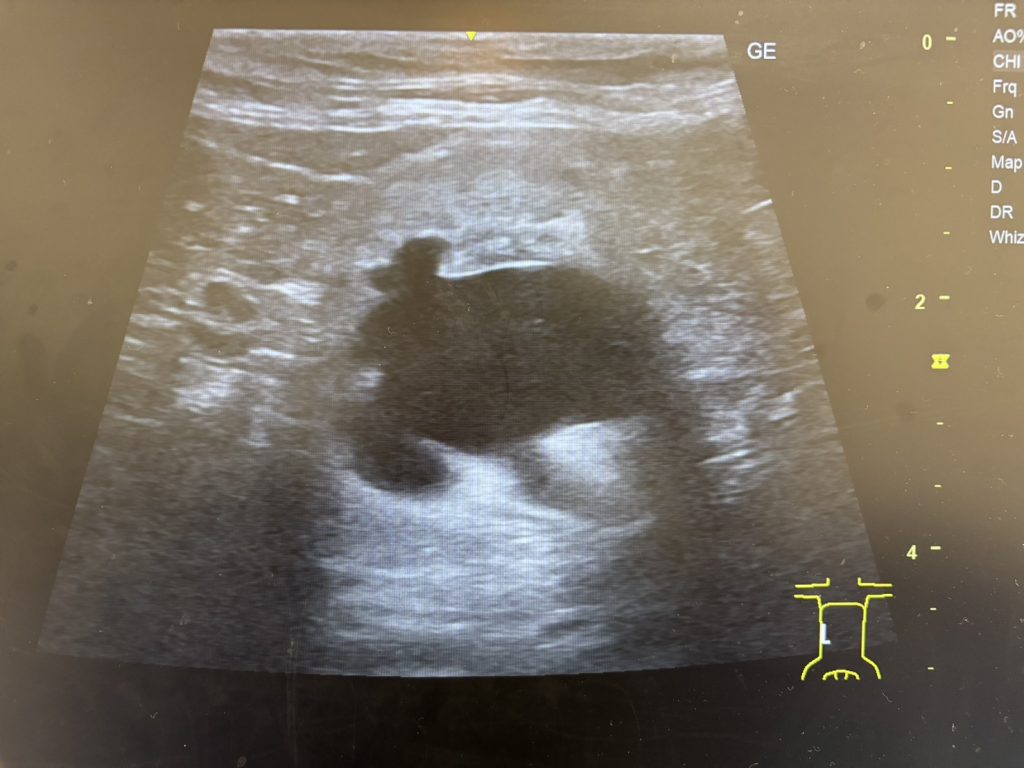

【水腎症を呈した猫の腎臓】

水腎症とは?

尿管が結石などで閉塞すると、腎臓で作られた尿が流れなくなります。

すると尿が腎臓の中にたまり、腎臓が腫れる状態になります。

この状態を水腎症(すいじんしょう)と呼びます。

水腎症が長く続くと腎臓に強い負担がかかり、腎機能が低下する可能性があります。

猫の尿管閉塞では、超音波検査でこの水腎症が見つかることで

尿管結石が疑われるケースも少なくありません。